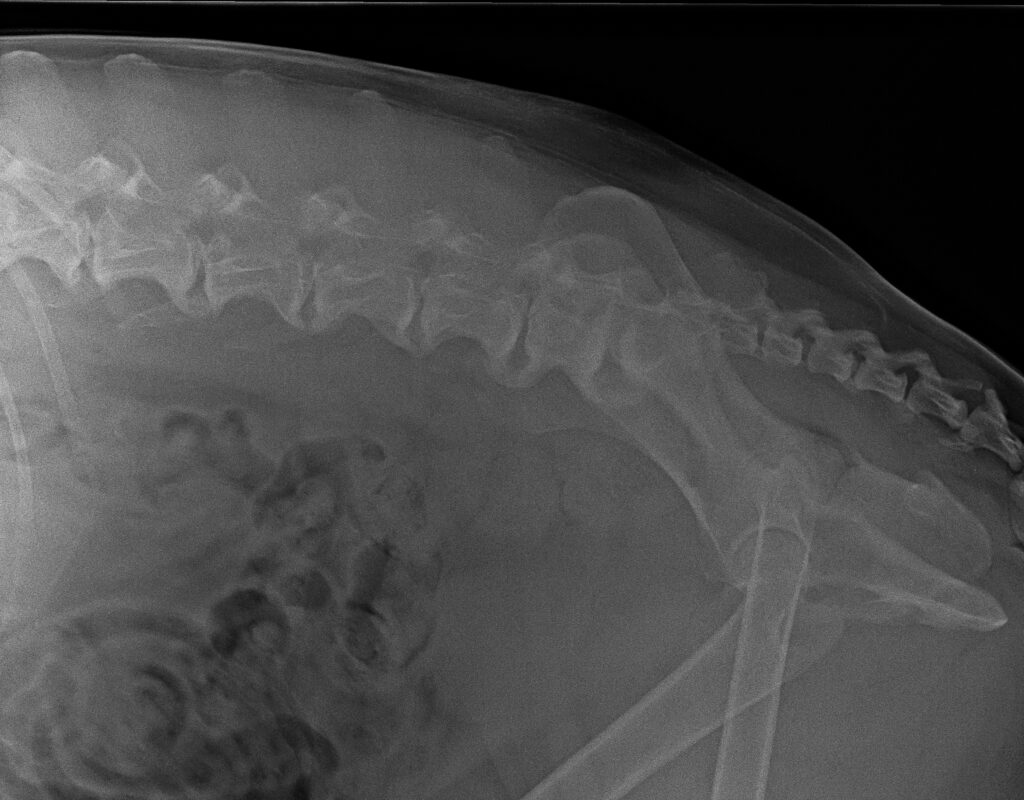

NEURALTHERAPIE

Bei vielen Hunden mit akuten oder chronischen Rückenproblemen wenden wir die Therapeutische Lokalanästhesie an. Dabei werden gereizte Nervenwurzeln, meist im Bereich der Lendenwirbelsäule, mit einem Lokalanästhetikum gezielt infiltriert.

Durch diese feinen Injektionen werden schmerzende Nervenreflexe kurzfristig unterbrochen. Das hilft dem Körper, Spannungen abzubauen und seine Selbstregulation wiederherzustellen.

Wir wenden diese Methode in unserer Praxis besonders bei Rückenschmerzen, Bewegungseinschränkungen und chronischer Verspannung an.